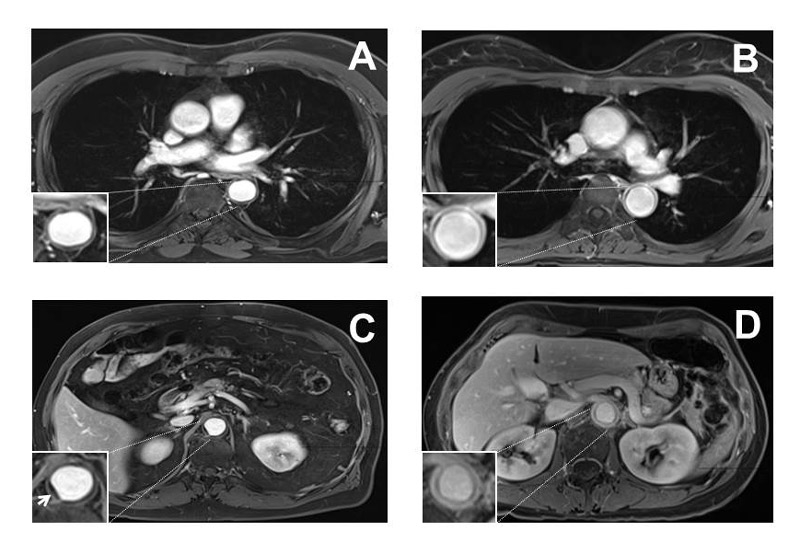

MRA examples are given in figure 1.

Figure 1 Examples of negative and positive magnetic resonance angiography (MRA) findings in the thorax and abdomen, each T-1 weighted images 10 minutes after administration of gadolinium-containing contrast medium. (A) Thoracic MRA without signs of vasculitis. (B) Thoracic MRA demonstrating vasculitis. (C) Abdominal MRA without signs of vasculitis, arrowhead pointing to atherosclerotic plaque. (D) Abdominal MRA demonstrating vasculitis.